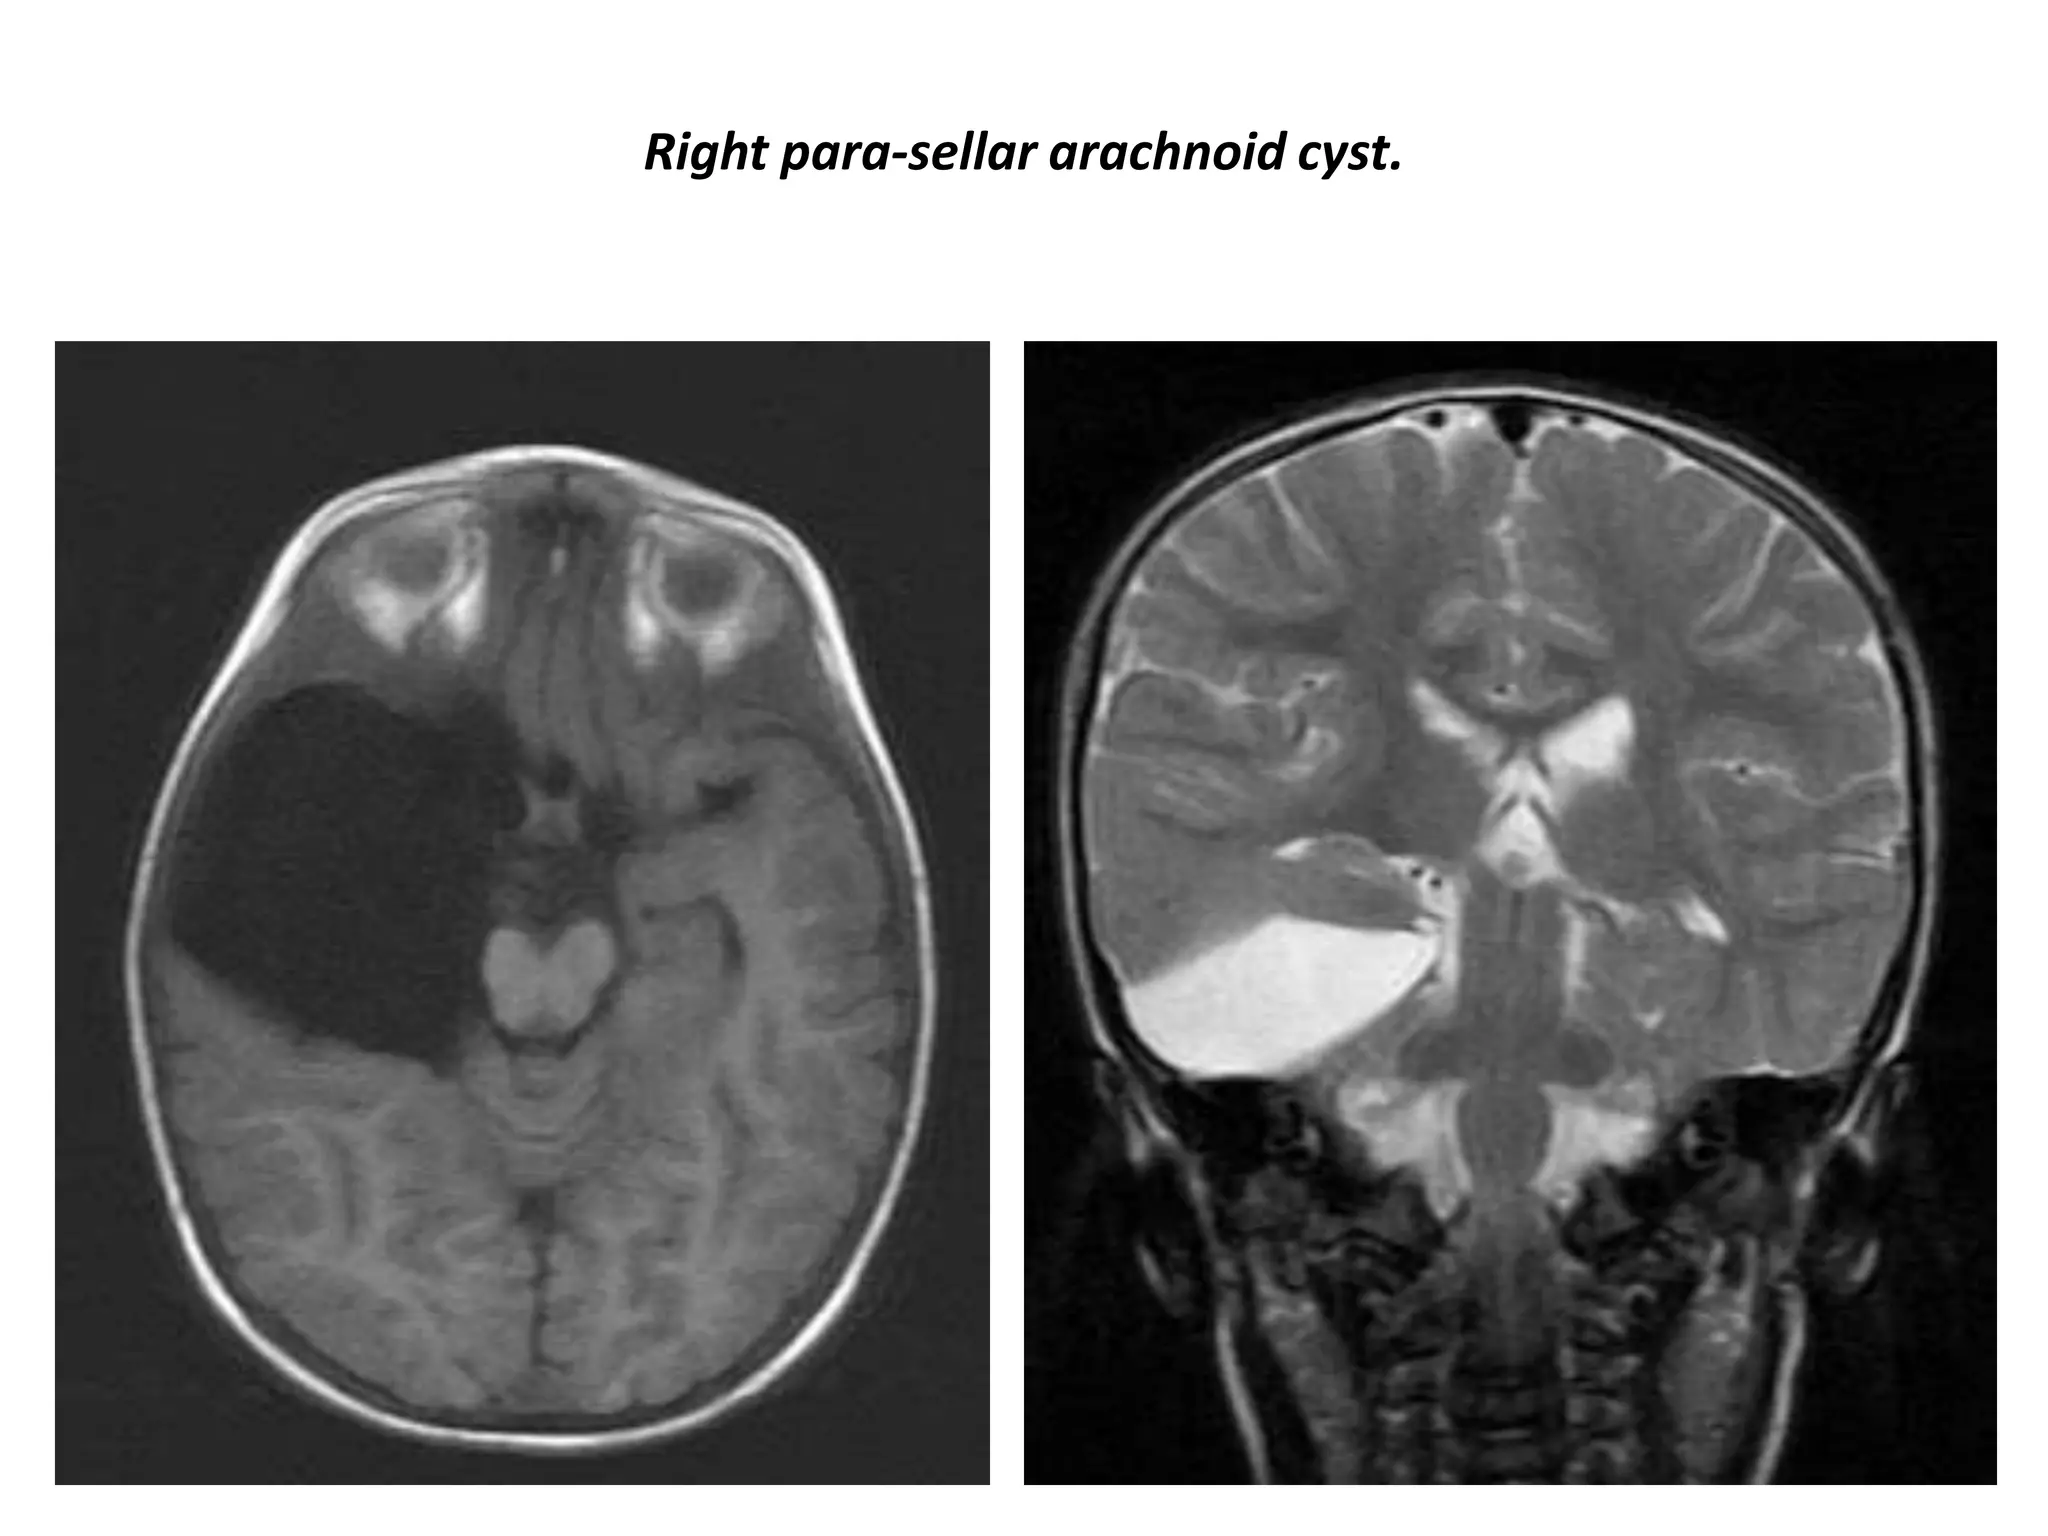

Right para-sellar arachnoid cyst.